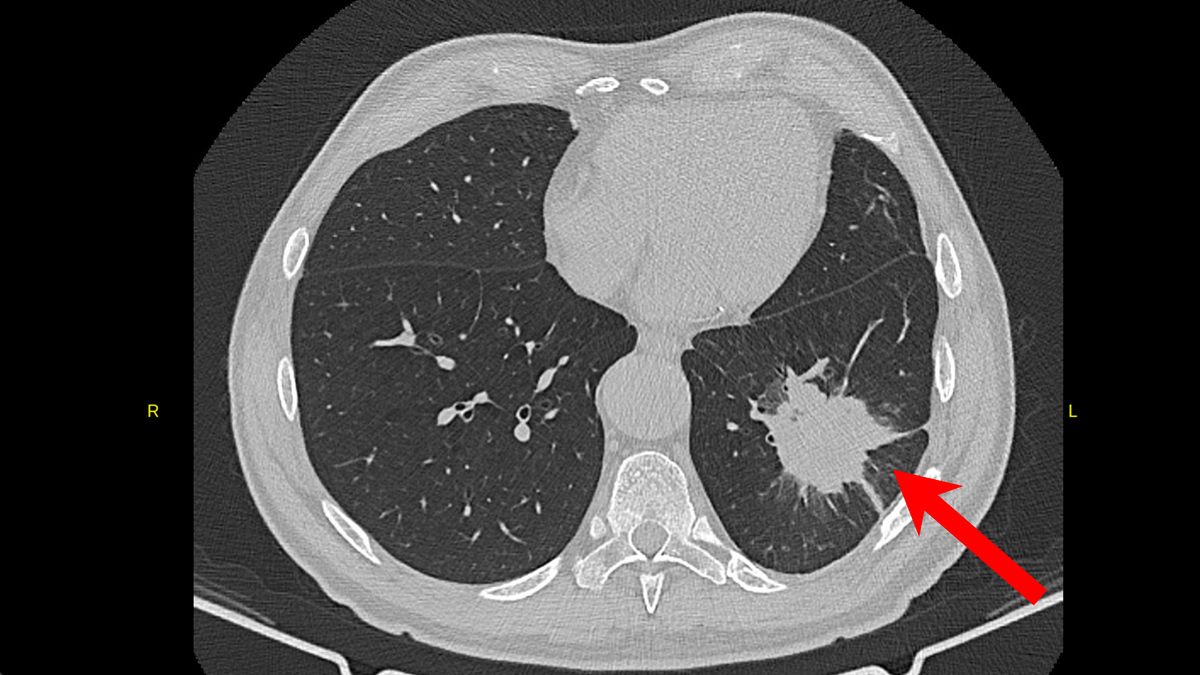

Мужчина 65 лет осенью 2024 года почувствовал себя плохо, стала подниматься температура до 38С, появился кашель с мокротой, иногда даже были прожилки крови. Обратился по месту жительства, был обследован терапевтом. По результатам анализов крови - воспаление, на КТ органов грудной клетки - следующая картина.

КТ органов грудной клетки при первичной диагностике

Из описания КТ ОГК:

Определяется наличие инфильтрата в S9 левого лёгкого, неправильной формы, размером до 53х47мм., с наличием периферической лучистости и тяжей к костальной и междолевой плевре.

Можно было бы сразу заподозрить опухолевый процесс, но врачей смутил следующий факт. Если пролистать снимки КТ чуть дальше, становится видна зона распада в данном инфильтрате, то есть признаки нагноения. На КТ это выглядело следующим образом.